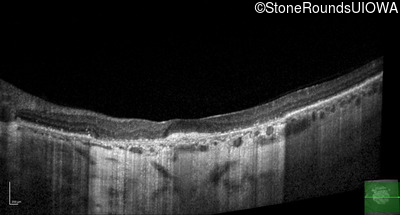

Optical Coherence Tomography - Right - 10/225

Exemplar / OCT Stack